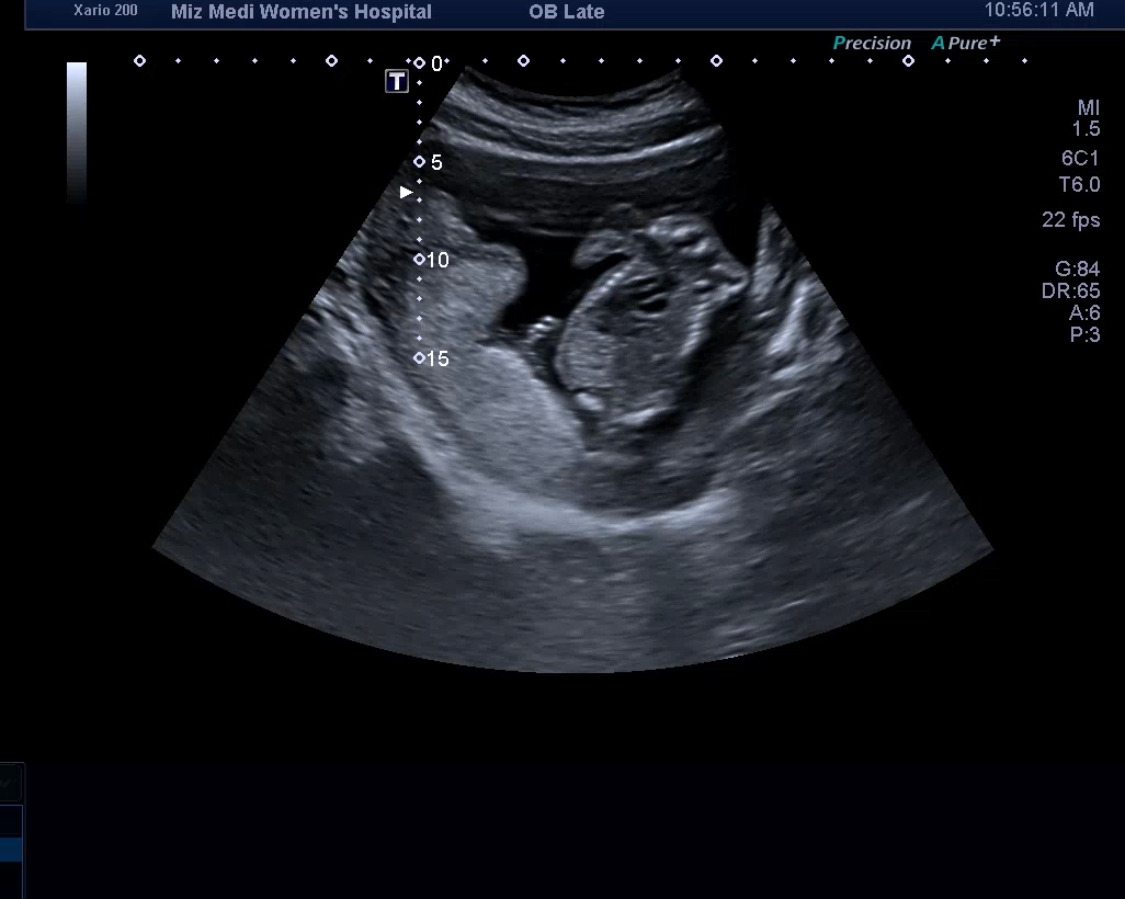

이전까지는 질초음파를 통해 아가를 봤었는데, 이제 배 초음파를 통해서 아가를 본다.

아가가 그만큼이나 컸다는 사실이 또 신기했다. 이 작은 생명체가 이렇게 하루하루 쑥쑥 내 배속에서 크고 있구나. 엄마는 너를 열심히 품고 있어야겠구나.

그렇게 의사 선생님께서는 머리, 다리, 팔, 배, 등 하나하나 봐주시면서 사이즈를 재주 시기 시작했다.

이제 아가가 커서 한 컷에 전체 모습을 담기가 어렵더라.

마지막에 마주한 우리 다올이 얼굴.....

이거 보고 엄청 웃었다. 아직 너무나 사람 같지 않아서...ㅋㅋㅋ 다올아 미안해.

엄마는 사실 널 보고 조금 무서웠어, 웃기기도 하고..

그래도 엄마는 널 사랑한단다. (그저 감정표현에 솔직한 엄마라는 것만 알아줘..)

16주차 얼굴.jpg